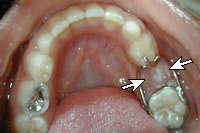

Space Maintainer

When a primary tooth is lost prematurely the teeth can drift into the new space crowding out the permanent tooth that is supposed to erupt into that space in the future. A space maintainer keeps baby teeth from shifting into the space where the tooth was lost so the permanent tooth can erupt in its natural proper space. As the permanent tooth erupts, Dr. Hickey or Dr. Hill will remove the appliance. Space maintainers can help eliminate the need for extensive orthodontics in the future.

band loop space maintainer

erupting tooth